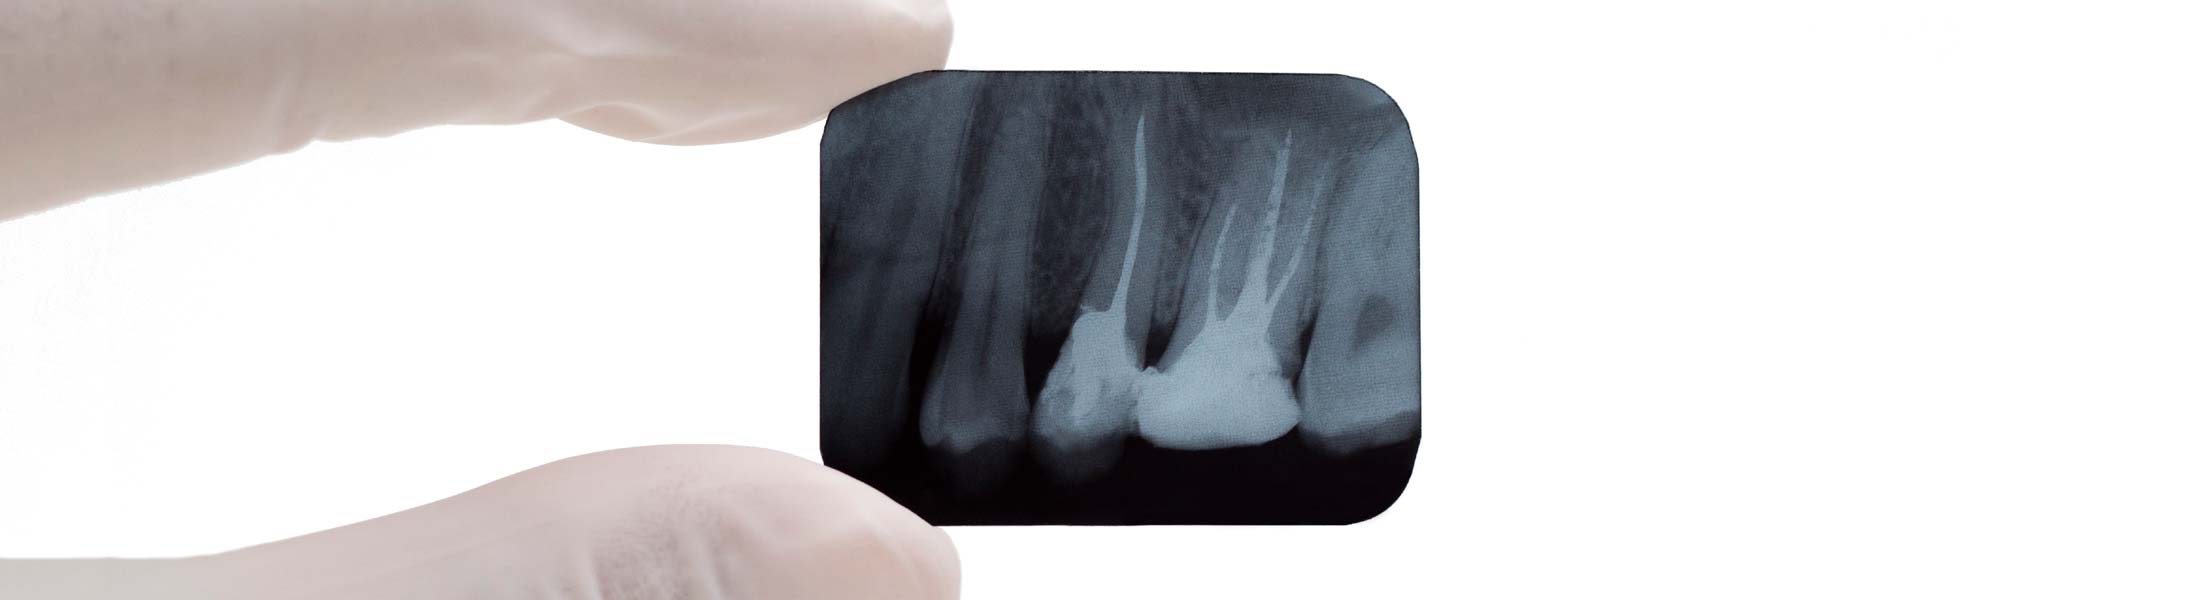

Bei einer endodontischen Behandlung des Zahnes wird der Zahnnerv, der durch Karies, Bakterien oder Entzündung erkrankt ist, therapiert. Um auch feine Wurzelkanäle aufzufinden, arbeiten wir mit elektronischer Längenmessung und Mikroskop. Bei Wurzelkanalbehandlungen erleichtert uns ein OP-Mikroskop die Einsicht in den Zahn. Auch feinste Kanäle können dargestellt und unter Sicht aufbereitet werden.

Ziel der Wurzelkanalbehandlung ist die Entfernung von Bakterien und restlichem Nervengewebe aus dem Kanal, die Reinigung und Desinfizierung, sowie das Auffüllen und der Verschluss des Hohlraumes. Um einen perfekten Verschluss zu gewährleisten wird Guttapercha erwärmt und mit Ultraschall verdichtet.

Während und nach der Behandlung werden Röntgenaufnahmen gefertigt, um den Behandlungsverlauf und den Erfolg zu kontrollieren und zu dokumentieren.